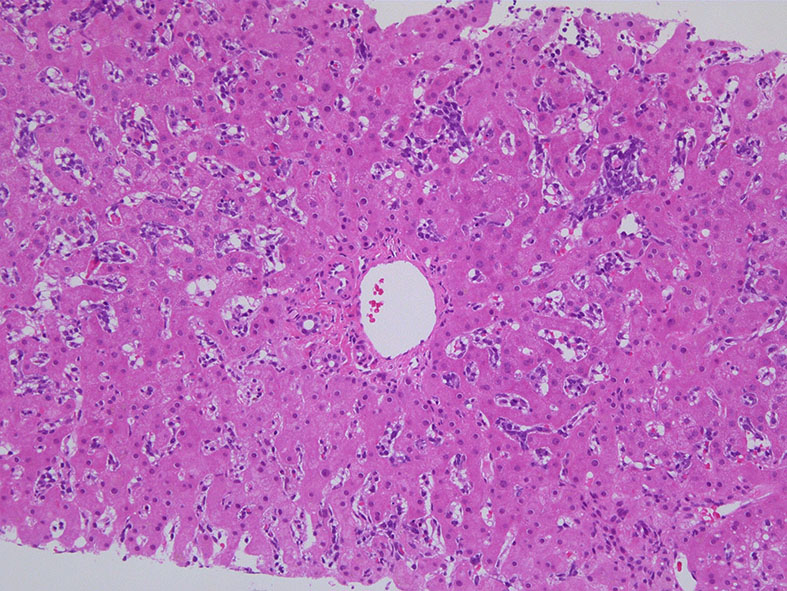

肝臓

肝針生検組織; 類洞に細胞浸潤が認められ, 非浸潤部との境界がぼんやりと認められる. 類洞と異なり, グリソン鞘は腫瘍細胞の浸潤が乏しいか, ほとんど認められない.

類洞内に浸潤増殖するリンパ腫細胞: 類円形・長円, 瓜状の核をもつ,細胞質の乏しい細胞(サムネイル画像のクリックで大きな画像が見られます)